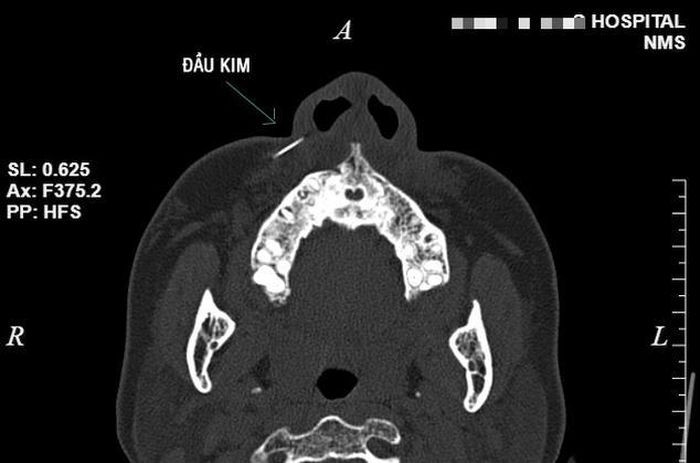

Bệnh nhân được chụp CT scanner cho kết quả hình ảnh dị vật khoảng 1 cm vị trí phần mềm cánh mũi phải. Chỉ định thủ thuật lấy dị vật được đưa ra. Bệnh nhân được về nhà trong ngày.

Hình ảnh đầu kim được lấy ra trên thực tế và hình ảnh chụp CT. Ảnh: BVCC